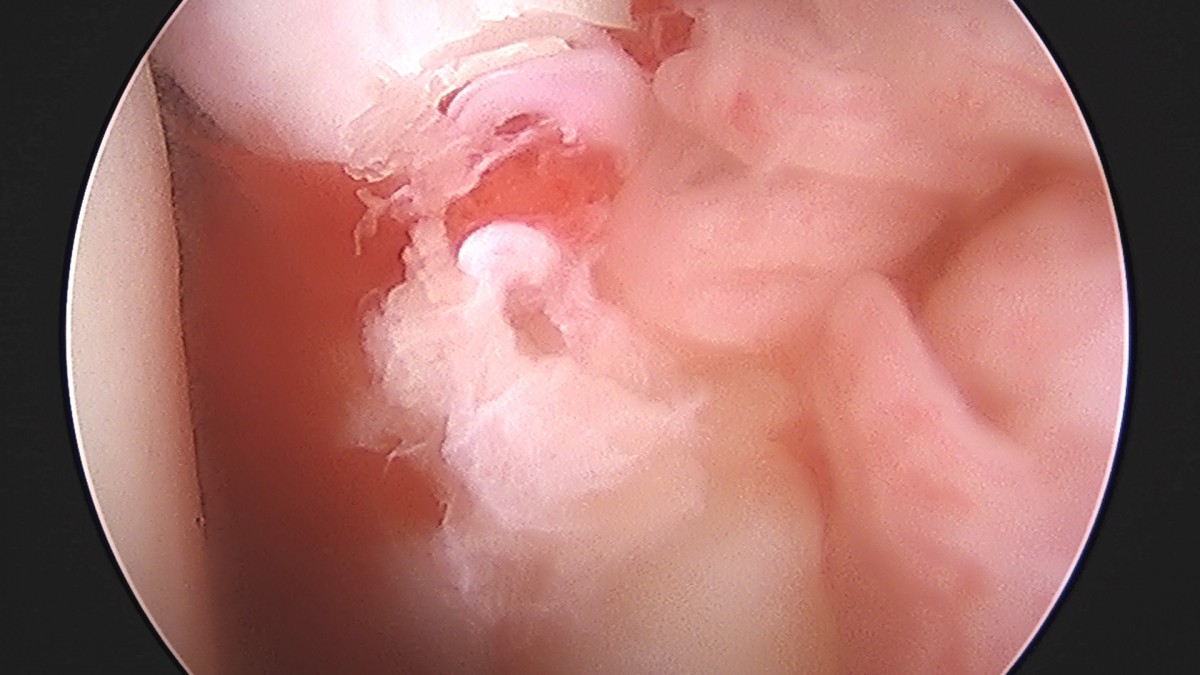

정지영원장님 어깨 관절낭 이완술 및 석회제거술 박설O 환자

작성자 최고관리자 댓글 0건 조회 732회 작성일 25-09-16 16:59